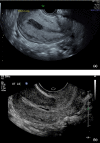

(a) Transvaginal sagittal image of the uterus in 32‐year‐old patient with acute endometritis 14 days after vaginal delivery demonstrates the subserosal hypoechoic rim and endomyometrial junctional indistinction. (b) Transvaginal sagittal image of the uterus in a 30‐year‐old female 3 days after surgical termination of pregnancy who was scanned to rule out RPOC demonstrates a small amount of debris in the endometrial cavity but the endomyometrial junction is well defined and no subserosal hypoechoic rim was identified by either reader.

(a) Transvaginal sagittal ultrasound image of a 41‐year‐old female with acute endometritis 14 days after vaginal delivery shows endomyometrial junction indistinctness as well as the subserosal hypoechoic rim sign. (b) Sagittal transvaginal ultrasound image of a 31‐year‐old female scanned to examine for RPOC following miscarriage demonstrates good definition of the endomyometrial junction and absence of the hypoechoic rim sign.